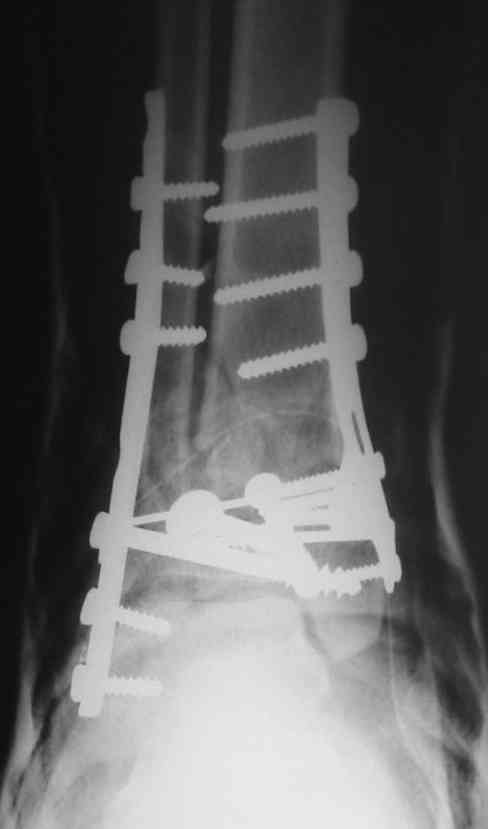

Это типичный перелом пилона, который надп лечить только открыто.Извини те что опоздал к обсуждению, но даже если вы уже оперировали больного по Илизарову это даже лучше.Посылаю картинки.

Посмотрим вроде прошло если понравится напишите расскажу как это сделать.По принципам АО кстати при поступлении сначала восстанавливают длину малоберцовой кости фиксируют пластиной 1/3 трубки потом накладывают аппарат наружной фиксации и через 7-10 дней открыто восстанавливают большеберцовую кость.С уважением Дрягин

На рентгенограммах типичный перелом пилона по типу С-3. есть опыт до 100 открытых опреаций у нас в клинике. 20 примерно в год. Принцип один -все внутрисуставные переломы нуждаются в открытой репозиции и внутренней стабильной фиксации. При поступлении КТ не надо, так как получается только нагромождение костей. Истинной картины нет. Главное восстановить длину малоберцовой кости - это ключ к успеху. При поступлении меньше всего надо думать о сосудистых расстройствах, т.к. сама операция и репозиция даже сначала частичная даёт улучшение сосудитых нарушений. Причём очень быстро. Операция в 2этапа. При поступлении доступ позади наружной лодыжки, причём обязательно. После этого репозиция малоберцовой кости и фиксация пластиной 1/3 трубки под винт 3,5. Дренаж и любой аппарат наружной фиксации. Затем после спадения отёка на 5-7-10 день аппрат снимается и дугообразный разрез спереди от медиальной лодыжки 10-12 см. Главной чтобы расстояние между 1 и вторым разрезом было не меньше 7-8 см. Тогда не будет некрозов лоскутов. Таранная кость используется как матрица на неё укладываются отломки и фиксируются пицами. Ренг-контроль. Отломки лежат все отдельно, но ничего не высыпется. При переломах С-3 всегда нужна костная пластика (из крыла). Фиксация пластиной лист клевера простой или LCP. Гипс не нужен. Дренаж до 48 часов. Операция длится 3-4 часа обязательно без жгута. Посылаю примерно такой же случай.

Послала ещё два снимка, если не пройдут, пошлю ещё. Дрягин. Если есть вопросы, готов ответить.